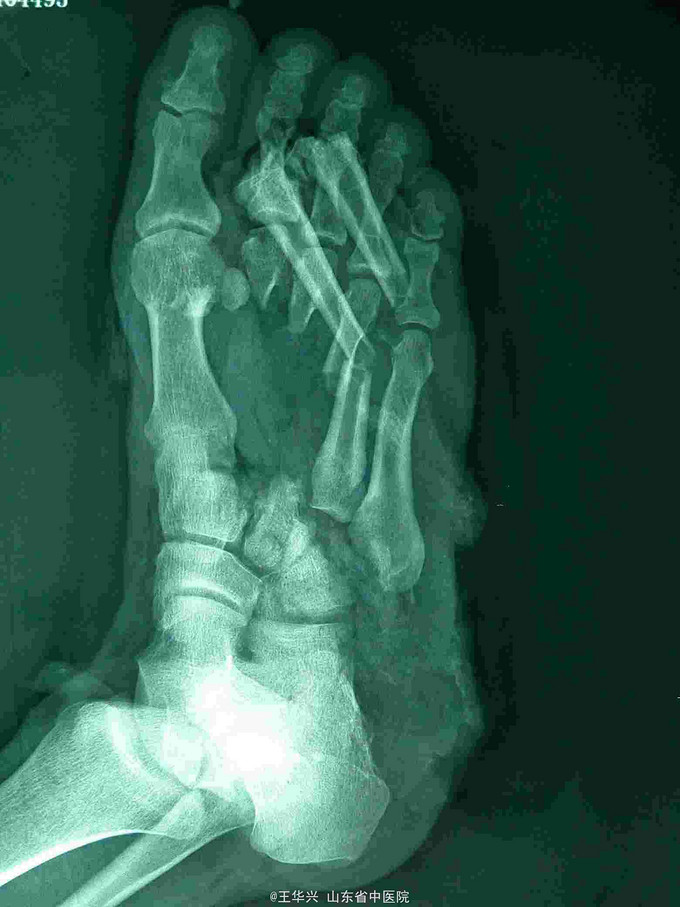

主诉:车祸致左足疼痛、活动受限并有大面积软组织损伤6小时。 现病史:患者6小时前因车祸致左足疼痛,活动受限伴有足背部大面积软组织损伤收住入院,急诊诊断为“左足毁损伤”。患者左足麻木感,大片足背软组织翻向外侧。

查体:左足疼痛,功能活动受限,伴有大面积软组织损伤,软组织向外侧翻转,足部前侧可见5*3cm软组织缺损,患处麻木感,足背动脉不可及。 辅助检查:x线 左足第2,3,4跖骨骨折